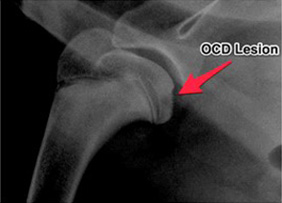

Osteocondrosi (OC) e Osteocondrite dissecante (OCD)

L'Osteocondrosi è una patologia caratterizzata dal fallimento dell'ossificazione all'interno di una zona cartilaginea di accrescimento che si può rilevare in diverse sedi. Ne consegue un'area d’ispessimento della cartilagine e successiva necrosi della cartilagine stessa. Dal punto di vista clinico, questa condizione non è dolorosa, interessa le epifisi in crescita, determina diversa lunghezza degli arti. Inoltre può guarire o progredire verso l’OCD, in caso di formazione di flap cartilaginei articolari associati ad alterazioni infiammatorie dell’articolazione. La causa esatta di questa patologia è ancora sconosciuta, sebbene vi siano un insieme di fattori che sarebbero implicati nella patogenesi dell’OCD. Tra questi fattori, ve ne sono alcuni genetici, quali la crescita accelerata, alcuni nutrizionali, quali ad esempio l’eccesso di proteine, calorie, calcio, fosforo, vitamina D e alcuni traumatici tra cui fattori ischemici, e persino fattori ormonali (es. testosterone) e alla stessa struttura anatomica dell’articolazione (incongruenza fisiologica).

L'OCD risulta quindi da una progressione dell’osteocondrosi, ed è caratterizzata dalla fissurazione della cartilagine ispessita che scopre l'osso subcondrale, dalla separazione del frammento cartilagineo che può rimanere ancora parzialmente attaccato oppure diventare un corpo libero articolare. Solitamente è una condizione dolorosa, dove è presente sinovite. La guarigione dipende dalla sede della lesione. Può essere un riempimento del difetto cartilagineo con tessuto fibroso o fibrocartilagine. In genere progredisce verso l'osteoartrosi.

Nella patogenesi dell’OCD è coinvolto l’ispessimento della cartilagine articolare, la quale non aderendo in maniera ottimale all’osso subcondrale è resa suscettibile di fenomeni di necrosi (dei condrociti più profondi), con conseguente mancanza di ossificazione della matrice cartilaginea. Quando si verifica un’applicazione di forze tra la scapola e l’omero, come durante la corsa o il salto, possono generarsi fessure orizzontali nella zona interessata. Se il trauma persiste, è possibile la formazione di fessure verticali, che fanno sì che il fluido sinoviale raggiunga gli strati più profondi della cartilagine in degenerazione provocando sinovite.

Se non sussistono ulteriori traumi, la lesione può risolversi, ma se continua può portare alla formazione di flap cartilaginei che continuano a causare sinovite fintanto che non vengono rimossi. I flap cartilaginei possono:

L’OCD colpisce più frequentemente gli animali giovani tra i 4-10 mesi d’età (la comparsa è possibile fino ai cinque anni) appartenenti a razze caratterizzate da crescita rapida, e gli esemplari maschi sono maggiormente predisposti. Può essere unilaterale o bilaterale (tra il 27% e il 68% dei casi) e in genere colpisce più di un’articolazione, il pastore tedesco, il golden retriever, il labrador retriever, il rottweiler, il San Bernardo e l’alano sono tra le razze più predisposte.

Le sedi in cui compare maggiormente l’OCD nel cane sono il terzo caudale della testa dell’omero (maggior frequenza), il condilo mediale dell’omero, il condilo femorale laterale e la troclea del talo. Con minor frequenza è possibile altresì la comparsa nelle faccette articolari vertebrali, nella testa femorale, nel bordo acetabolare, nella cavità glenoidea e nel radio distale.

Clinicamente gli animali possono presentare zoppia da leggera a moderata e a volte intermittente, che peggiora in seguito a esercizio.